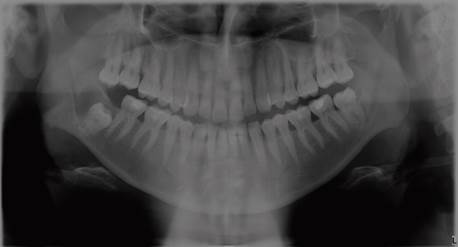

En la radiografía panorámica en el cual se hizo el hallazgo (Figura 1), se observa una imagen radiolúcida, redondeada, de límites definidos en relación a la corona del diente 4.8, que está incluido. En la tomografía computarizada cone beam, tomada al ingresar a nuestro servicio, se observa progresión de la lesión, con desplazamiento de la pieza dentaria a borde basilar mandibular. También es posible observar que este aumento de volumen respeta la anatomía mandibular, no perfora tablas ni hay evidencia de rizalisis (figura 2).